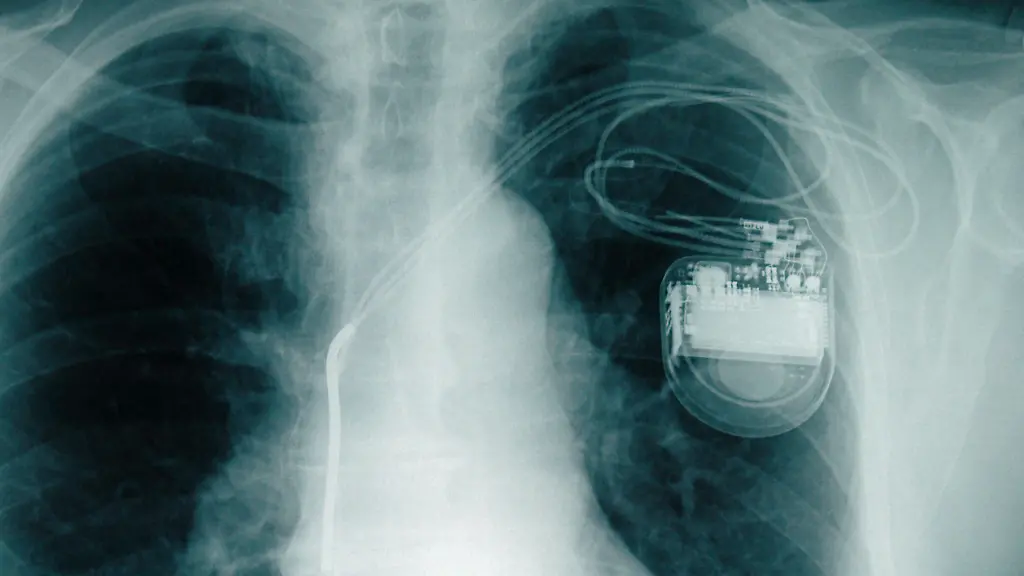

Strom aus Herz und LungeHerzschrittmacher kommt ohne Batterie aus

Die Einsetzung eines Herzschrittmachers zieht weitere Operationen nach sich: Geht die Batterie zur Neige, muss sich der Patient erneut unters Messer legen. Eine Erfindung aus den USA könnte das bald ändern. Das neue Gerät ist in der Lage, eine alternative Stromquelle anzuzapfen - die Organe.

Batteriewechsel bei Herzschrittmachern und anderen elektronischen Implantaten könnten künftig der Vergangenheit angehören. Ein US-Forscherteam hat ein Gerät entwickelt, das aus der natürlichen Bewegung von Organen genug elektrische Energie gewinnt, um etwa Herzschrittmacher dauerhaft zu betreiben. Das berichten die Wissenschaftler um John Rogers von der University of Illinois in Urbana-Champaign in den "Proceedings" der US-Nationalen Akademie der Wissenschaften ("PNAS").